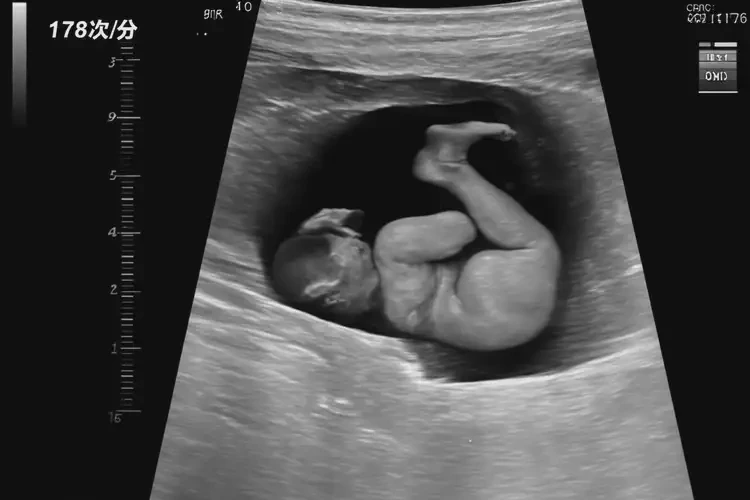

孕9周3天胎心176还要保胎吗

胎心率176次/分钟在孕9周3天属于正常范围,通常无需特殊保胎措施。

胎心率是指胎儿心脏每分钟跳动的次数,是评估胎儿健康状况的重要指标之一。在孕早期,胎心率通常较快,随着孕周的增加会逐渐减慢。根据医学研究,孕9周时胎心率的正常范围为140-180次/分钟。胎心率176次/分钟落在正常范围内,通常无需过度担心或采取特殊保胎措施。

孕9周3天胎心176还要保胎吗(图1)